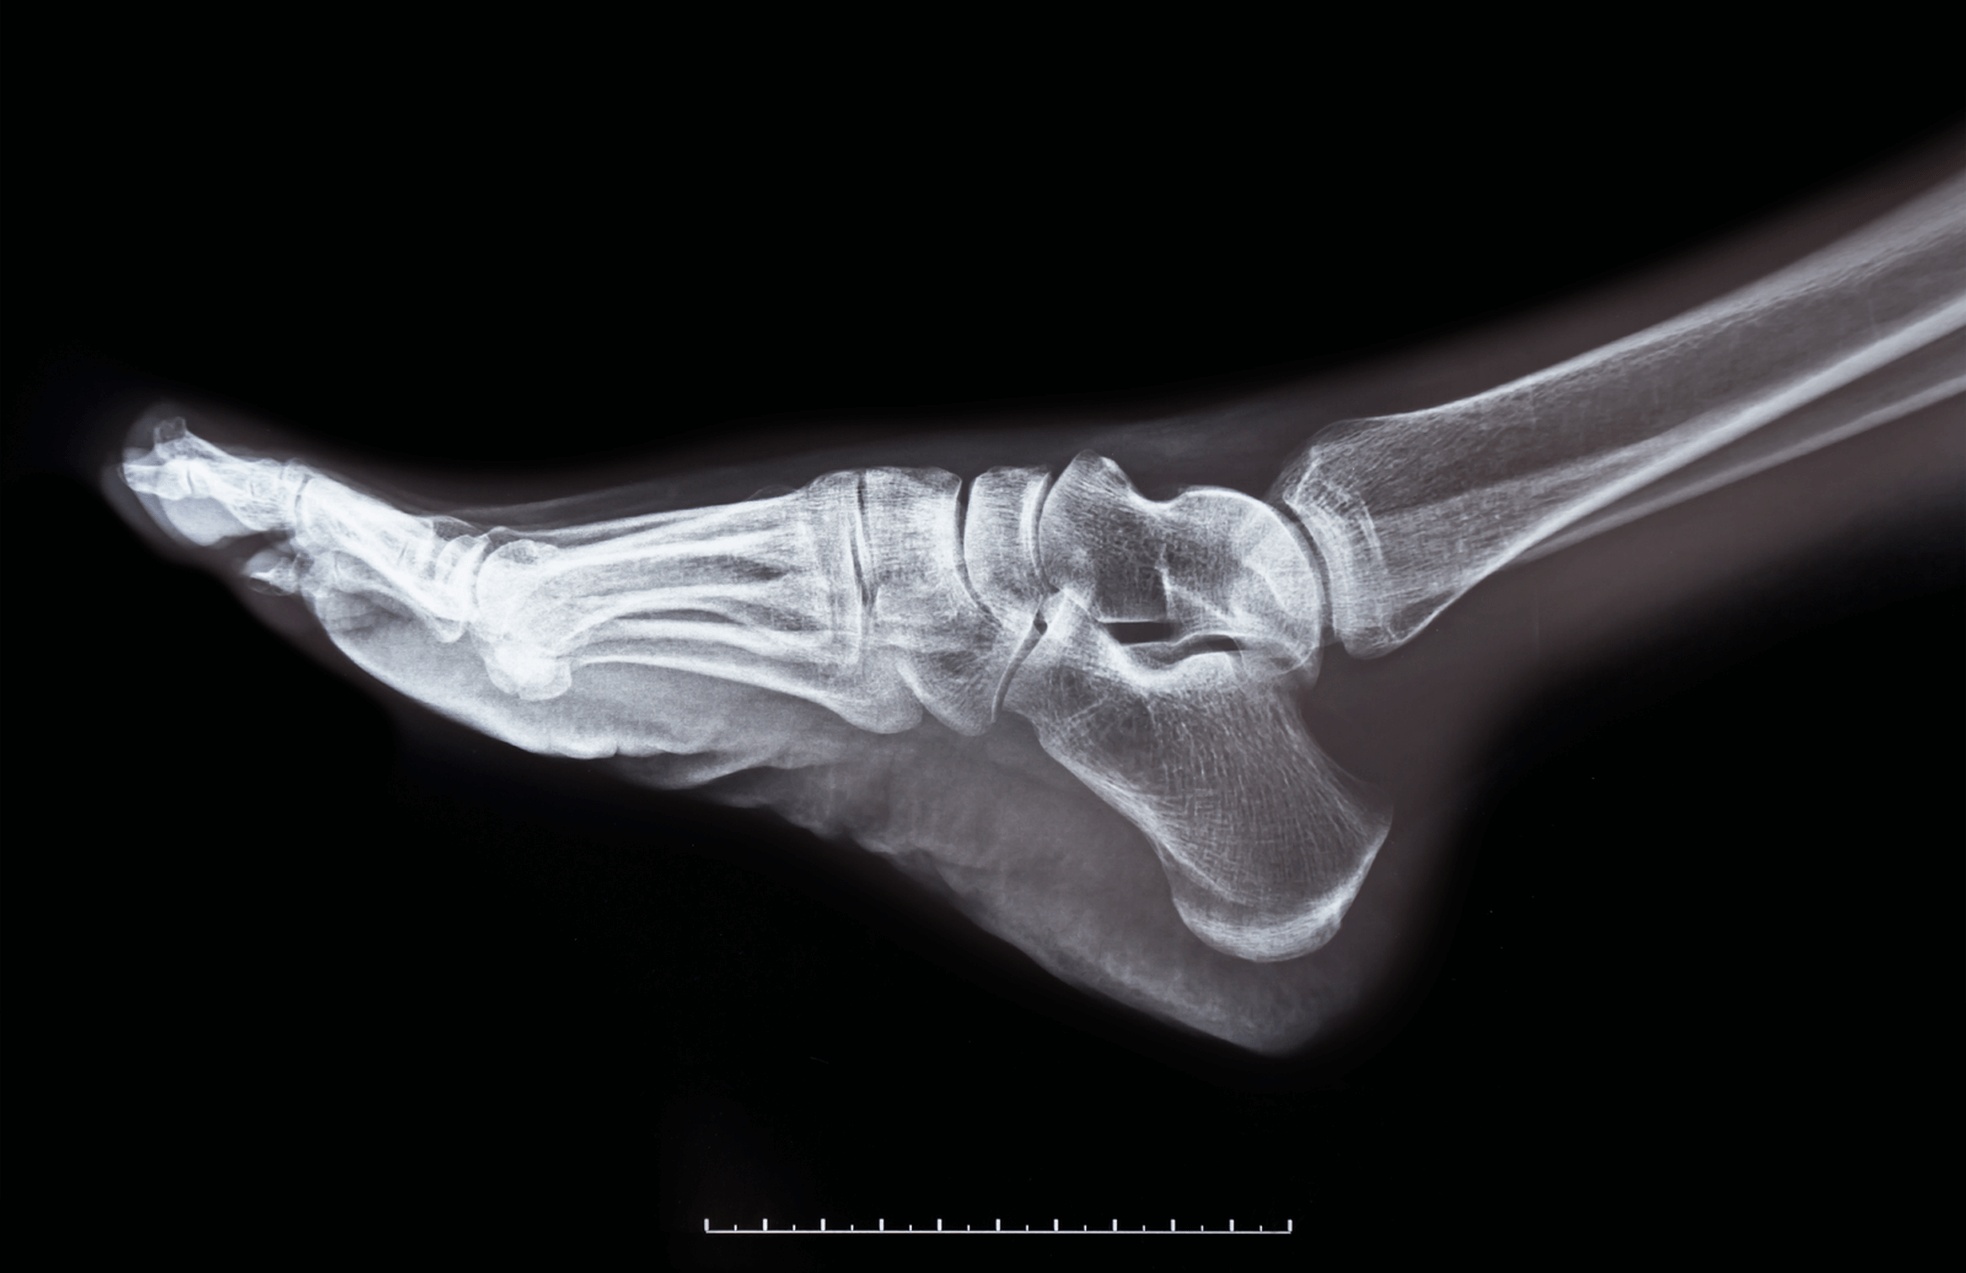

If you’re experiencing chronic pain in your big toe joint, seeing a podiatrist is your first step to a pain-free life. During your appointment, the foot specialist will likely perform a physical examination, possibly order X-rays, and discuss treatment options ranging from custom orthotics to surgical intervention based on your specific condition and lifestyle needs.